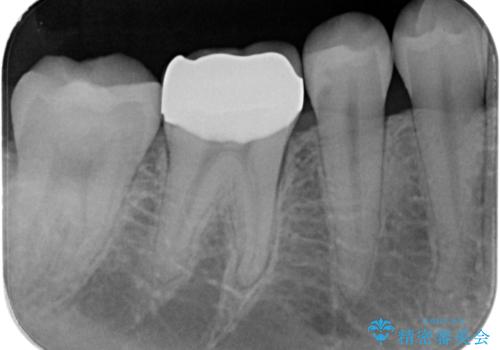

- 右下の保険治療での樹脂の劣化、および歯と歯の間の虫歯をセラミックのつめもので治療しました。

右下6番はセラミックのアンレーが入っていましたが、強度の問題もあり、やり直し後はクラウンとしました。